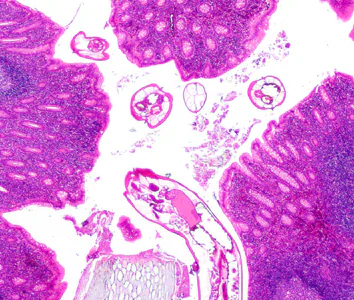

2015 DPDx Case Studies

DPDx Case Studies – 2015

DPDx is an educational resource designed for health professionals and laboratory scientists. For an overview including prevention, control, and treatment visit www.cdc.gov/parasites/.